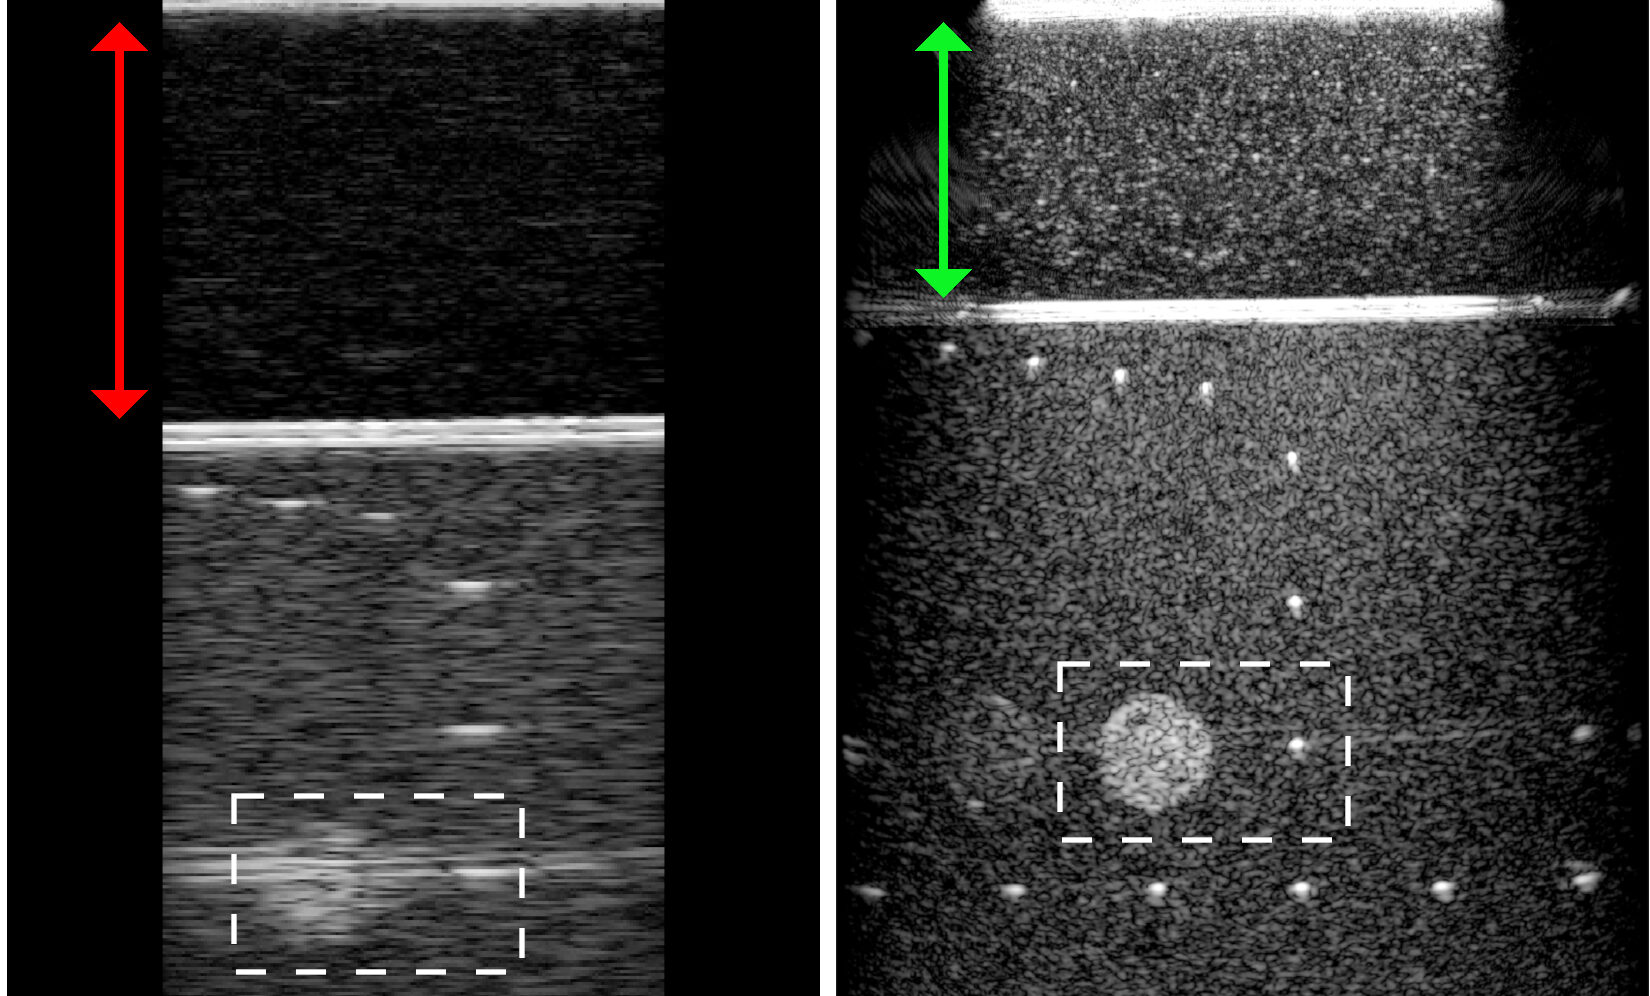

2020Physical Review Applied pubblica l’articolo “Seismic Imaging Method for Medical Ultrasound Systems” nel quale il gruppo Imaging and Numerical Geophysics del CRS4 valida con successo l’idea di applicare un metodo ondulatorio della sismica di riflessione al campo biomedico.

Il nuovo algoritmo migliora considerevolmente la risoluzione delle immagini ecografiche, grazie all’utilizzo di un modello matematico più complesso e più aderente alla realtà fisica rispetto a quelli sinora implementati nei software degli ecografi.

test di laboratorio effettuati rivelano una notevole risoluzione spaziale e un posizionamento estremamente accurato delle strutture illuminate.